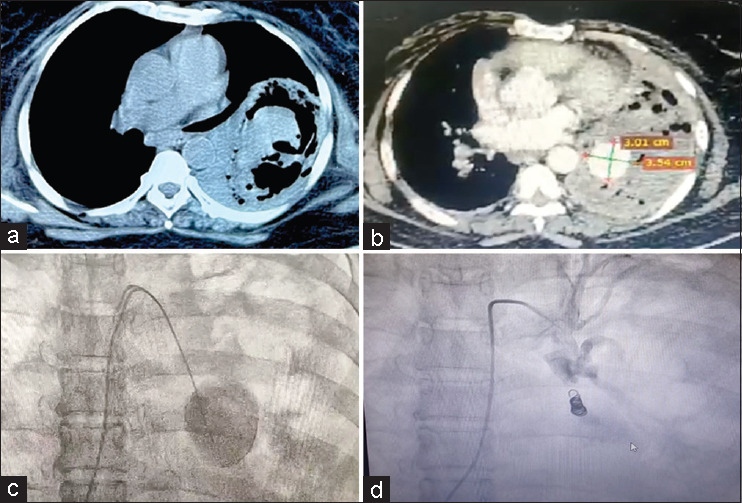

Necrotizing pneumonia causing left descending pulmonary artery pseudoaneurysm: A rare entity.

坏死性肺炎引起左降肺动脉假性动脉瘤:罕见病例。